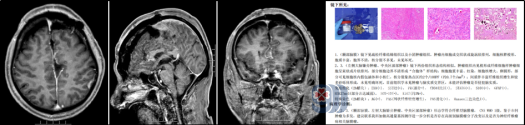

面对复杂的病情,欧阳辉教授带领三九脑科医院神经外十科团队进行了充分的术前讨论,制定了周密的手术方案。在征得王先生和家属的同意后,手术如期进行。术中,专家们凭借着精湛的显微神经外科技术,在精准保护重要神经和血管的前提下,成功将多发肿瘤(大的如鸽蛋,小的如蚕豆)一一摘除。

术后,王先生恢复良好,第一时间复查头颅MR显示:肿瘤已绝大部分切除。 切下来的肿瘤组织被迅速送往病理科进行检验,最终的病理报告为:形态学符合纤维型脑膜瘤, CNS WHO 1级。 这个结果让所有人松了一口气。WHO 1级属于良性肿瘤,生长缓慢,预后良好。术后,王先生神志清醒,能够很好地遵医嘱完成各项动作指令,恢复顺利。